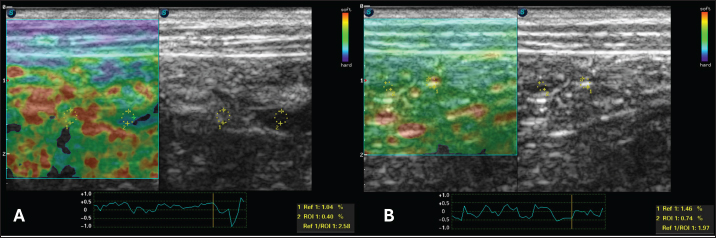

An abdominal ultrasound was performed using SAEVO® FT422 equipment with an 8.0-MHzz multi-frequency microconvex transducer. Gastric thickening (0.71 cm) was observed in the accessible portions, with preserved stratification and a mucosal layer containing intramural gas, suggesting gastritis and gastric pneumatosis. The duodenum and jejunum were also thickened (0.56 and 0.40 cm, respectively), maintaining their layered pattern. The intestinal mucosa exhibited thickening and hyperechogenicity, with coalesced hyperechoic echoes on the luminal surface (Fig. 1A), indicating inflammation associated with lymphangiectasia. Additionally, an enlarged jejunal lymph node was noted, characterized by regular margins, homogeneous echotexture, preserved echogenicity, and dimensions of 4.63 × 1.53 cm (Fig. 1B).

For the static qualitative assessment, the proximal segments of the duodenum and jejunum were analyzed in a longitudinal ultrasound section, and a heterogeneous distribution was found between the dorsal and ventral regions of the intestine, with patterns ranging from predominantly blue with some greenish parts and reddish foci (Fig. 2). To obtain the semiquantitative parameters, the region of interest (ROI) was drawn using the device’s software cursor. Initially, a reference, ROI 1 was obtained in the mesentery adjacent to the intestines, and ROI 2 was drawn in the dorsal region of the duodenum and jejunum. The drawings were similar and circular with the same depth and horizontal direction in the cross-section. The drawings were based on the diameter of the animal’s intestinal mucosa, and the force applied was guided by the elastographic compression wave. The strain ratio (SR) was obtained by calculating the ratio between the ROIs. The values for the duodenum were as follows: ROI 1=1.04 % and ROI=0.4%, with an SR of 2.58 (Fig. 3A). In the jejunum, ROI 1 measured 1.46 %, ROI 0.74 %, and SR 1.97 (Fig. 3B).

Fig. 1. B-mode ultrasound of a dog with intestinal lymphangiectasia. A: Duodenum with hyperechogenic mucosa at the dorsal and ventral margins. B-Jejunal lymph node with regular margins, homogeneous echotexture, and preserved echogenicity.

Fig. 2. Color elastography in double projection with a B-mode ultrasound image of a longitudinal scan of the proximal jejunum. The submucosa, muscularis, ventral, and dorsal serosa are red-green; the ventral and dorsal mucosa are blue-green.

Fig. 3. Semiquantitative cross-sectional deformation elastography of the intestine of a dog with intestinal lymphangiectasia. The SR was obtained by evaluating ROI 1 of the mesenteric and ROI 2 of the dorsal region of the intestinal segment. A duodenum with an SR of 2.58 B-Jejunum with an SR of 1.97